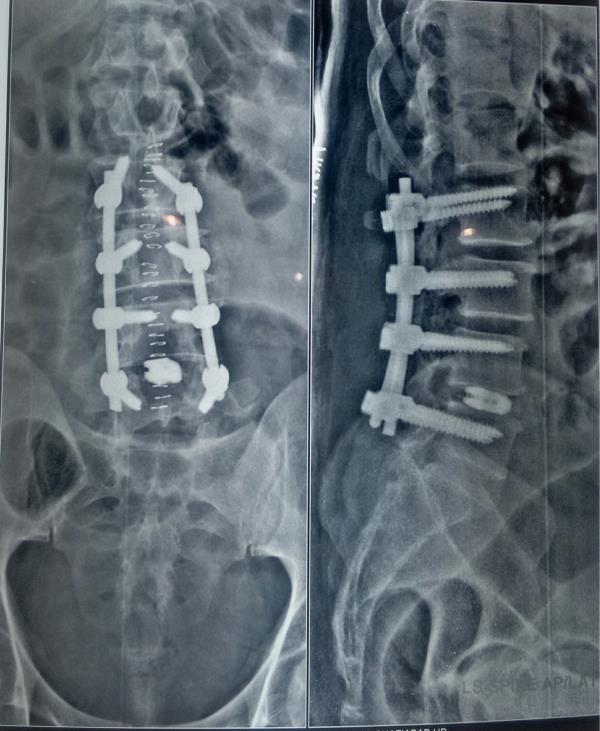

View DetailsDr Pramod Saini, Consultant Spine Surgeon

View DetailsBest spine surgeon in noida